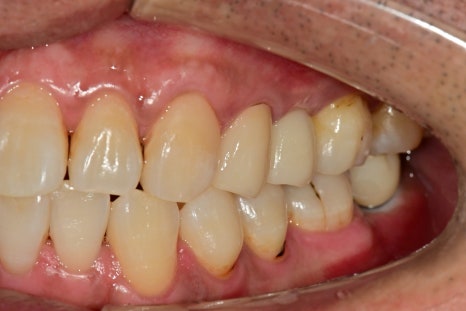

보철치료까지 완성될 때쯤은 임플란트의 고정력이 좋아질 시기와 비슷하여

비슷한 시기에 보철치료까지 완성할 수 있었습니다.

사진으로 요약해서 볼 때는 짧게 느껴지지만

기다리는 시간까지 하면 치료 기간은 반년 정도 걸렸습니다.

하지만 결과를 보면 심미, 기능적 측면에서 완벽하게 개선된 것을 보면

치료받으시는 분들도 그동안 내원하셨던것을 잘했다고 말씀해주시는것을 보면